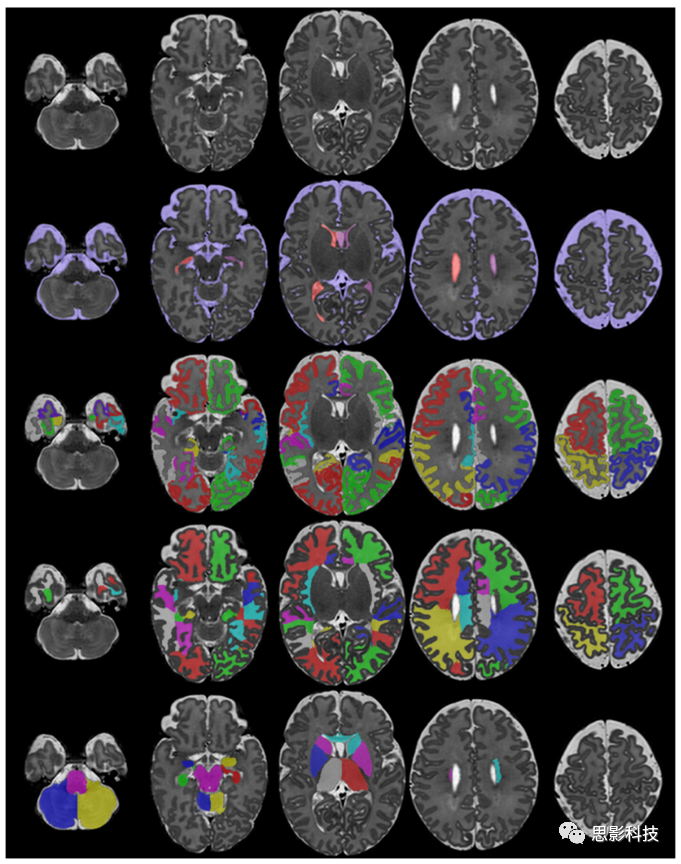

對大腦局部結(jié)構(gòu)的繪制比較困難,這是因為缺乏細(xì)致的的手工分割圖譜。早期的方法是基于人工放置在腦軸上的CGMWM區(qū)域的分割。這些軸將CGM / WM分為16個部分:額葉、中央前、中央和枕骨區(qū),分為左右半球的上半部和下半部。Oishi等人(2011)和Gousias等人(2012)手動描繪了大腦的第一個區(qū)域圖譜?,F(xiàn)有的分割方法使用這些圖譜或從成人圖譜中的label來描繪嬰幼兒大腦的區(qū)域結(jié)構(gòu)。使用成人大腦結(jié)構(gòu)的label進(jìn)行分割可能會出現(xiàn)問題,因為發(fā)育中的大腦可能尚未形成不同的大腦結(jié)構(gòu)。圖8中展示了了分割為不同結(jié)構(gòu)的示例。

8.使用Draw-EM的新生兒MRI結(jié)構(gòu)分割的示例。